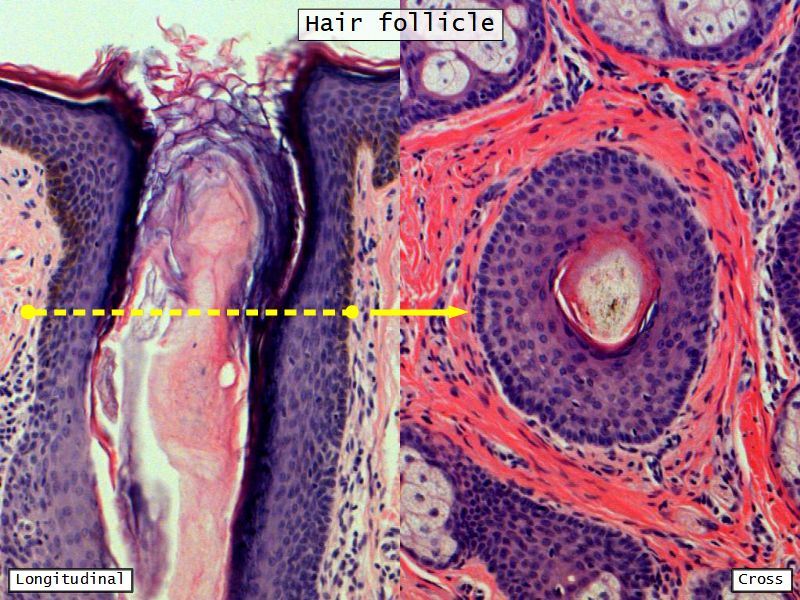

Fill in all the missing labels, and assess as you move through the slides. Answers on the down slide. It is important to do this using pen and paper, and not just glance through the images.